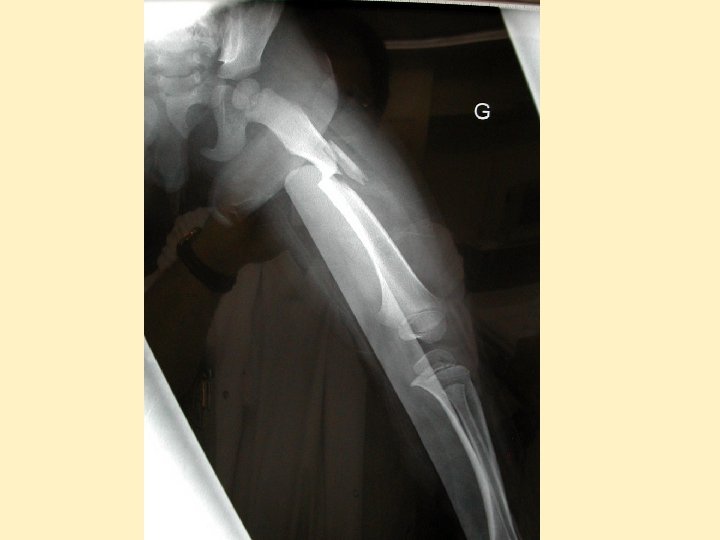

Lésions orthopédiques • Très fréquentes, souvent associées • Pronostic fonctionnel +++ • N'engagent pas le pronostic vital, sauf bassin (<5%) • Fémur seul ne peut expliquer une hypovolémie • Traitement chirurgical +++ si TC grave

Lésions abdominales - Assez rares: 20 à 30% des lésions - Lacérations hépatiques et spléniques - Traitement conservateur en milieu spécialisé - Lésions de désinsertion: mésentère, reins - A évaluer et réévaluer : clinique trompeuse